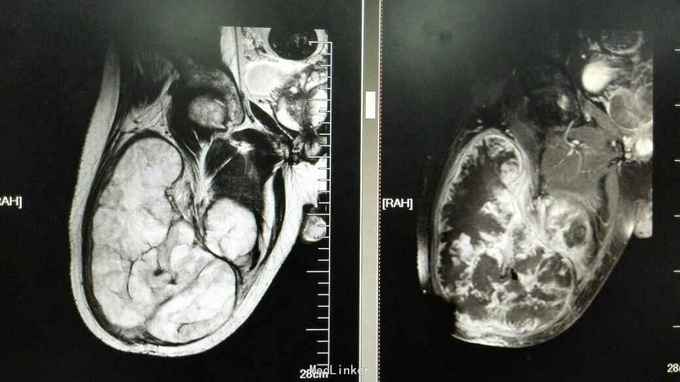

查体:右膝稍肿胀,皮温正常,右膝髌上囊处压痛(+),右膝屈曲稍受限(0~100度),余查体正常。 辅助检查:血常规、ESR、CRP正常 膝关节正侧位片:右膝关节退行性变,髌上囊肿胀 膝关节MRI提示:右膝髌上囊软组织占位,侵犯至股四头肌,考虑滑膜肉瘤可能性大 关节镜取活检提示滑膜肉瘤 全身PET-CT未见其它部位转移,肺无转移

诊断:右膝关节滑膜肉瘤 治疗:右大腿中上段截肢术